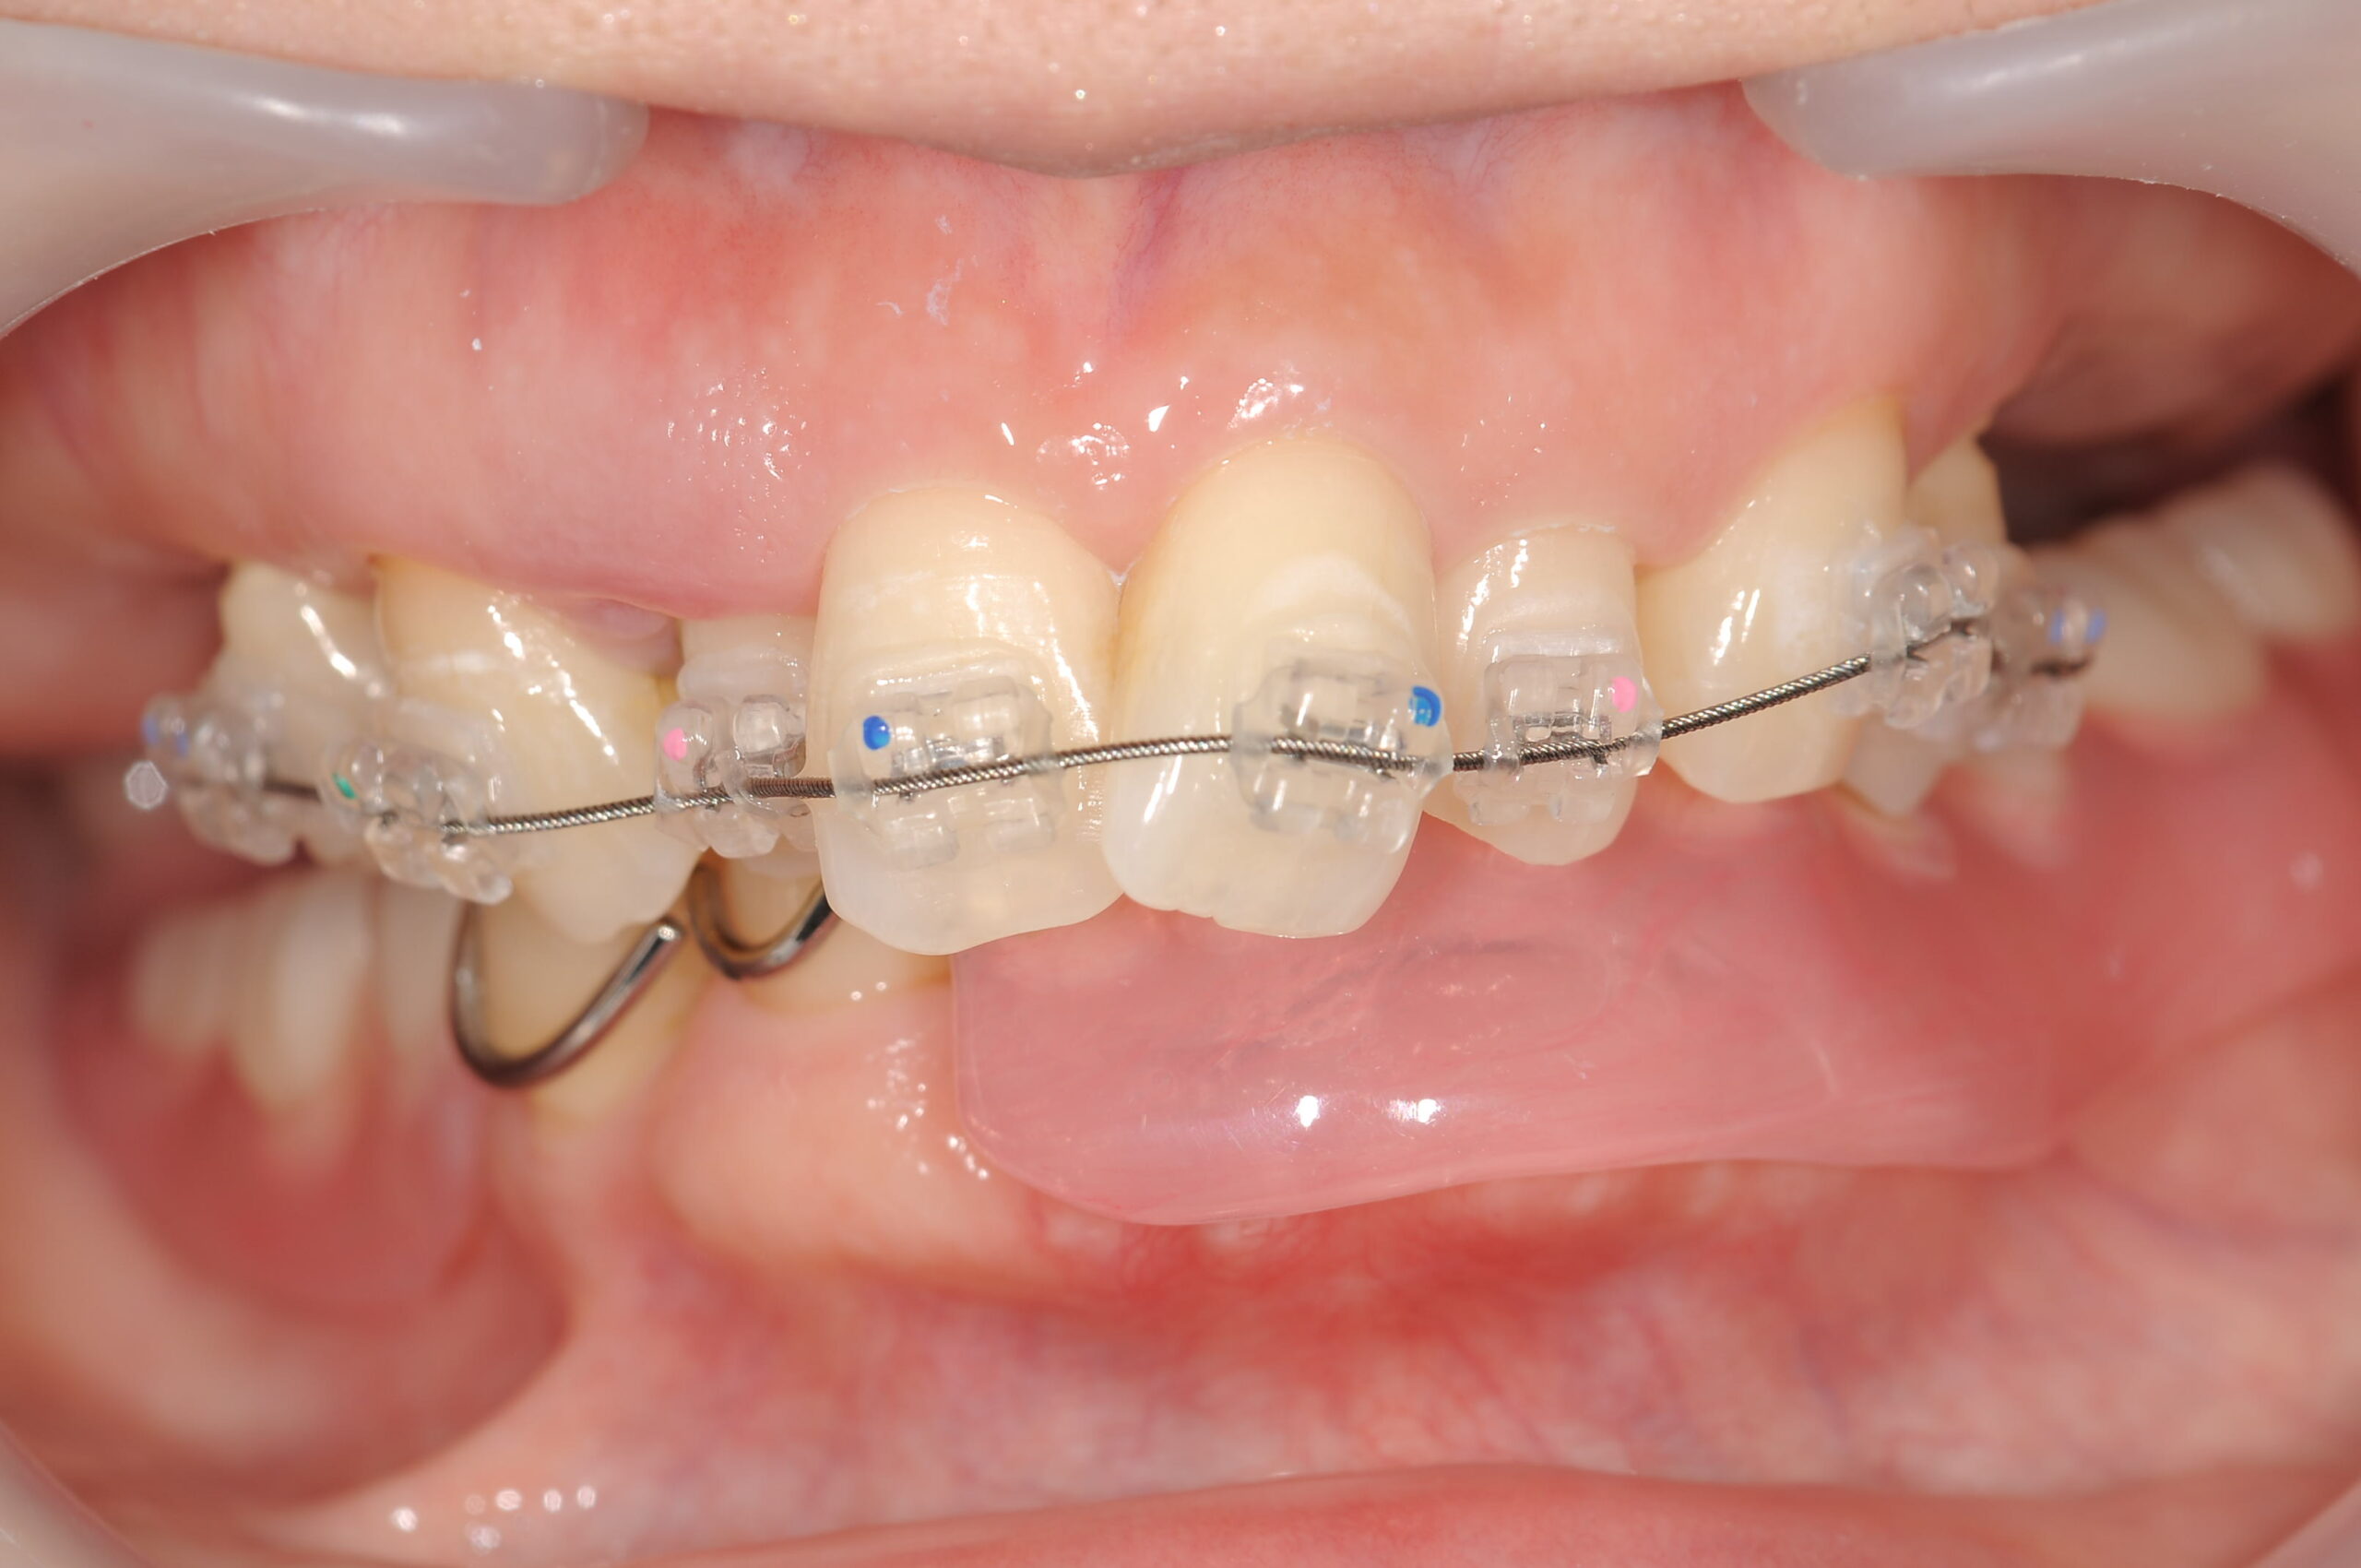

下あごには、取り外しの仮義歯を使っていただきながら、上顎は歯列矯正を行いました。

下あごにと上顎の両側にインプラントの仮歯が入り、歯列矯正により歯並びもよくなりました。